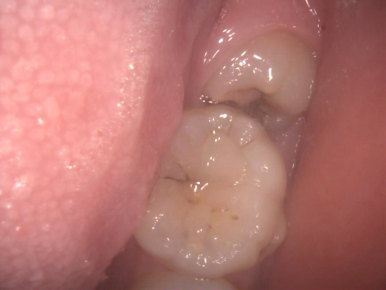

5.いつも汚れていて、口臭の原因と考えられます

左端の歯が親知らずです。ブラッシングが難しく、沢山磨き残しがあります。手前の歯も虫歯になっています。

一番奥の歯が親知らずです。汚れがたまって腫れています。